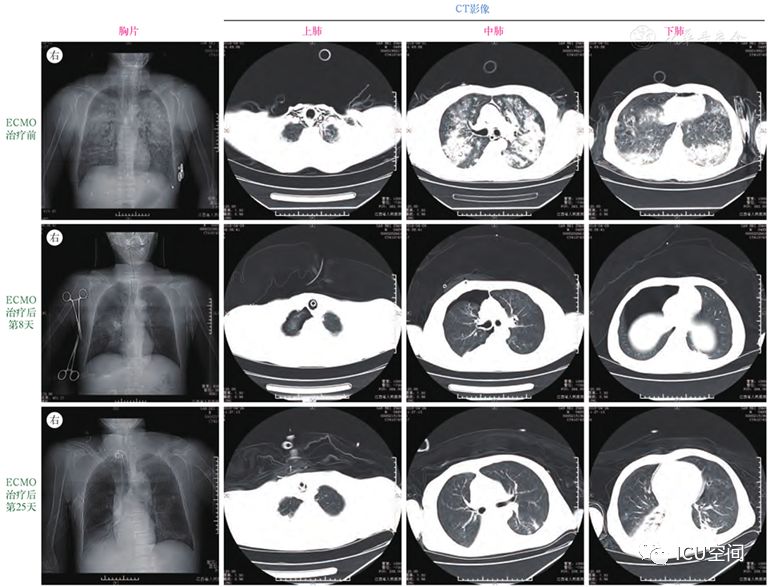

ecmo治疗急性光气中毒致急性呼吸窘迫综合征附4例报告